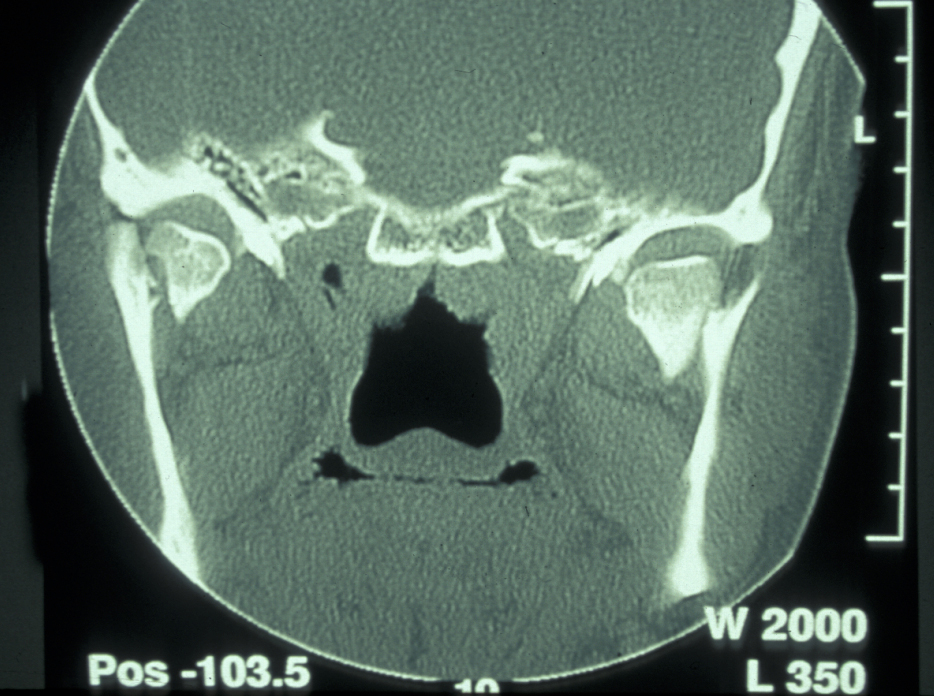

Plain film X-ray radiographs from different angles (occipitomental views) give some information, but a much more accurate assessment of the extent of the fracture can be obtained from CT scans (see Figure 11 for an example).

Figure 11: CT scan of a midface fracture.